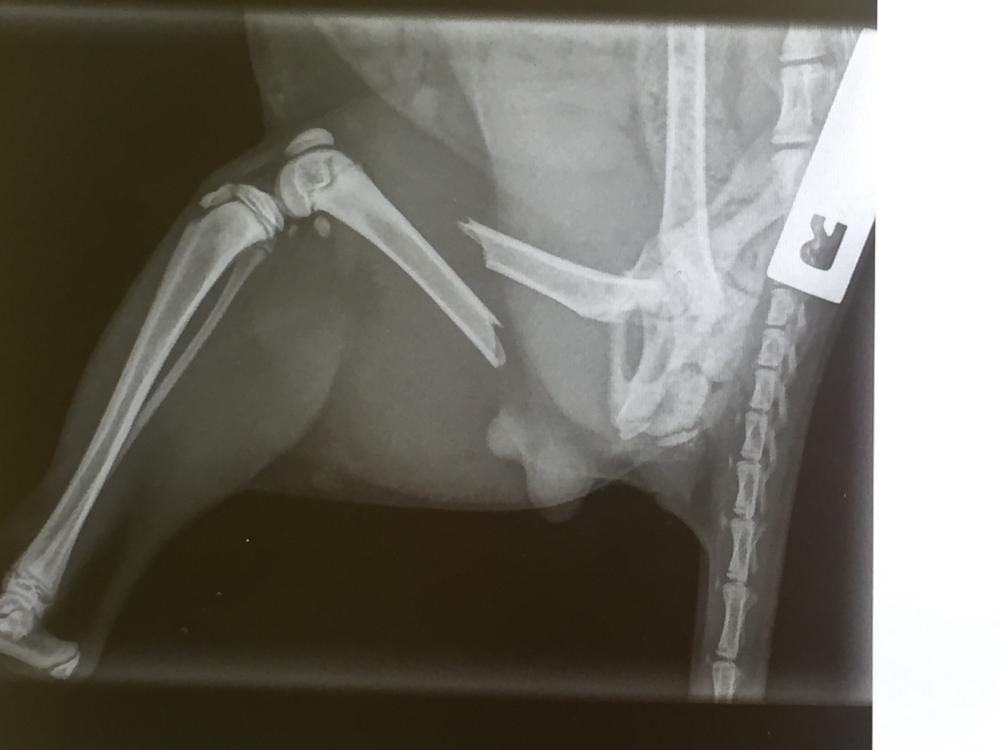

I’m needing help with vet bills for my 4 month old kitten Maui. It’s looking like someone has kicked him :(

He needs surgery and fast on his leg or he will be put down. I’m trying everything I possibly can to avoid getting him put down as his sister is here and they are so close to each other. I lost my 14 year old cat a year ago, my 5yr old cat not long after and I don’t want to loose this boy, I have a 3year old daughter that is gutted.